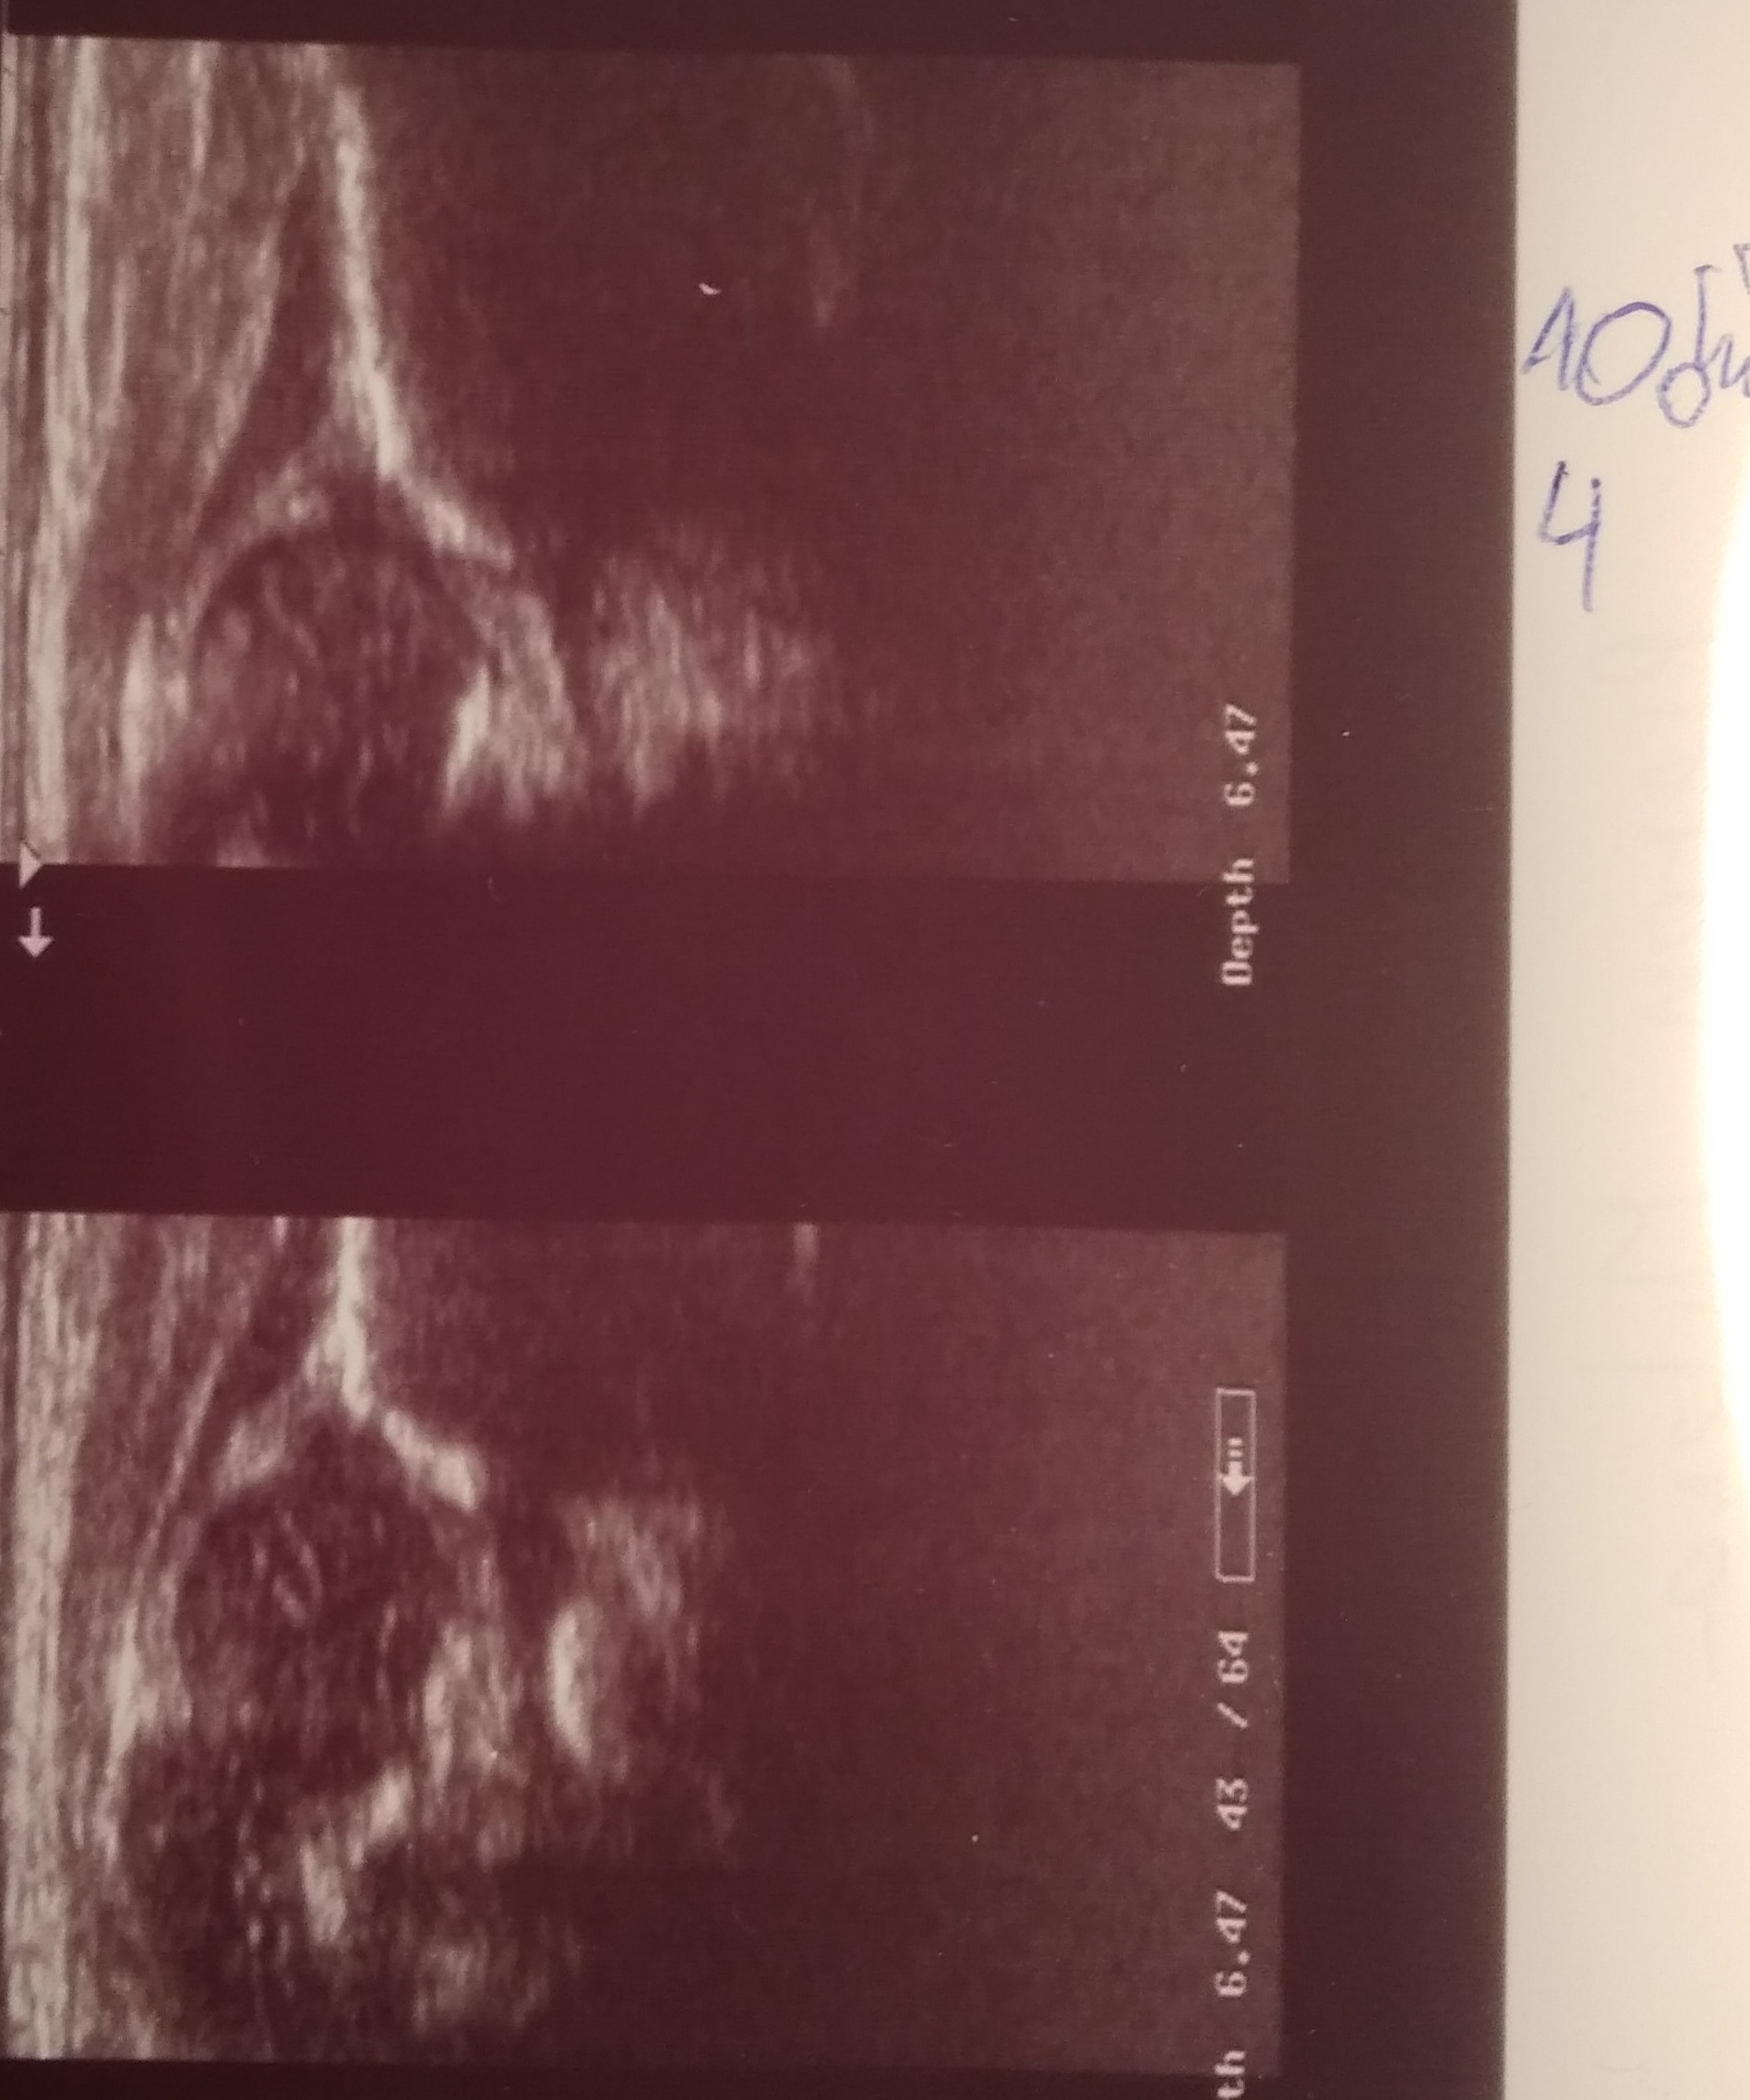

TYP P IIA L D (gorny L) kontrola za 2 dni

10 dzien dalej profilaktyka 17 godz

Typ P IIA L D ( gorny L)